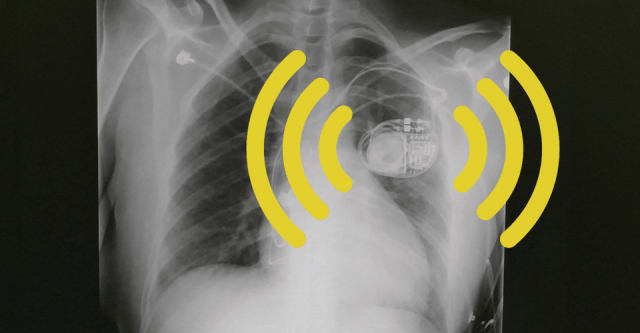

Cloud-connected medical devices save lives, but also raise questions about privacy, security, and oversight. Who has access to your pacemaker? Can any hacker fiddle with the settings or turn it (and thus you) off for good? Did the producers of these devices even consider such scenarios?

(Image from the Guardian article)